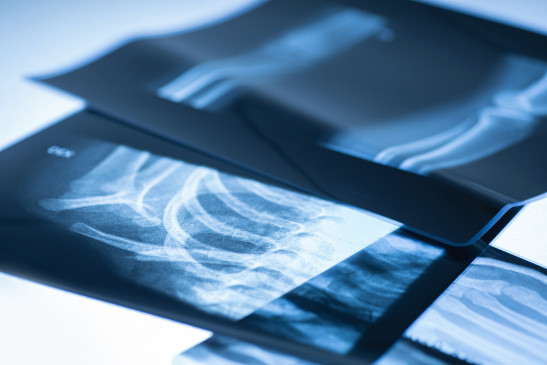

Röntgenaufnahmen gehören auch heute noch zu den unverzichtbaren Methoden der medizinischen Bildgebung – besonders, wenn es um die schnelle Abklärung von Knochenbrüchen, Gelenkveränderungen oder Veränderungen im Brustraum geht. In unserer Praxis in Bonn setzen wir dafür auf moderne digitale Röntgentechnik, die eine exzellente Bildqualität bei möglichst geringer Strahlendosis ermöglicht.

Röntgenstrahlen sind elektromagnetische Wellen, die in der Röntgenröhre künstlich erzeugt werden. Sie haben die Fähigkeit, Körpergewebe zu durchdringen und werden dabei – je nach Dichte und Zusammensetzung – unterschiedlich stark abgeschwächt. So entsteht ein kontrastreiches Bild, das uns wichtige Hinweise auf krankhafte Veränderungen liefert.